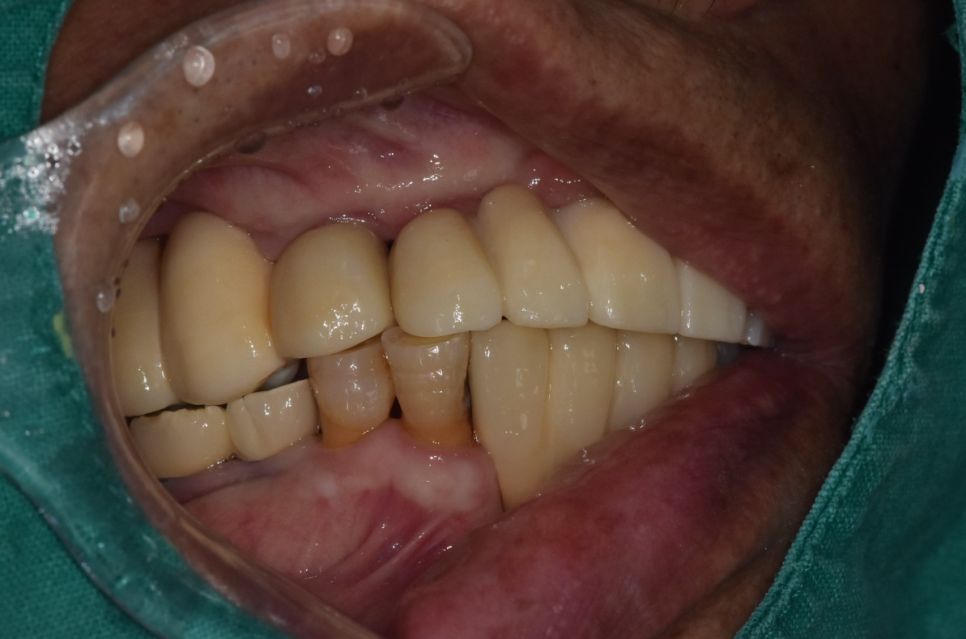

240706

이런 느낌입니다.

윗니가 아랫니를 덮은 정상 교합이죠